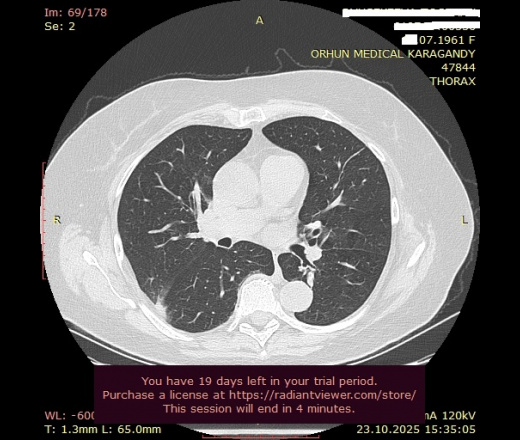

Может ли данный очаг (ТЭЛА?): "В верхней доле (S2) правого легокого, субплеврально по задней поверхности, участок уплотнения инфильтративного характера, плотностью 9HU, неправильной формы, размерами 3,2х0,7х4,8 см, с нечеткими неровными контурами, с признаками частичной консолидации легочной ткани" - вызвать то расширение легочного ствола, который Вы заметили?

Добрый день, уважаемый Мурат Максутович! Если коротко, то - может. А если описать данные изображения, как "участок субплевральной консолидации с нечеткими контурами, основанием прилежащей к плевре, перифокальное "матовое стекло", наличие бронхососудистых тяжей", так рука сама собой выведет "КТ-картина в большей степени соответствует ТЭЛА и инфаркту легкого (инфаркт-пневмонии), рек УЗИ вен нижних конечностей, КТ ОГК с в/в КУ), но вся эта стройная картина также может как подтвердиться, так и рассыпаться в результате дообследования